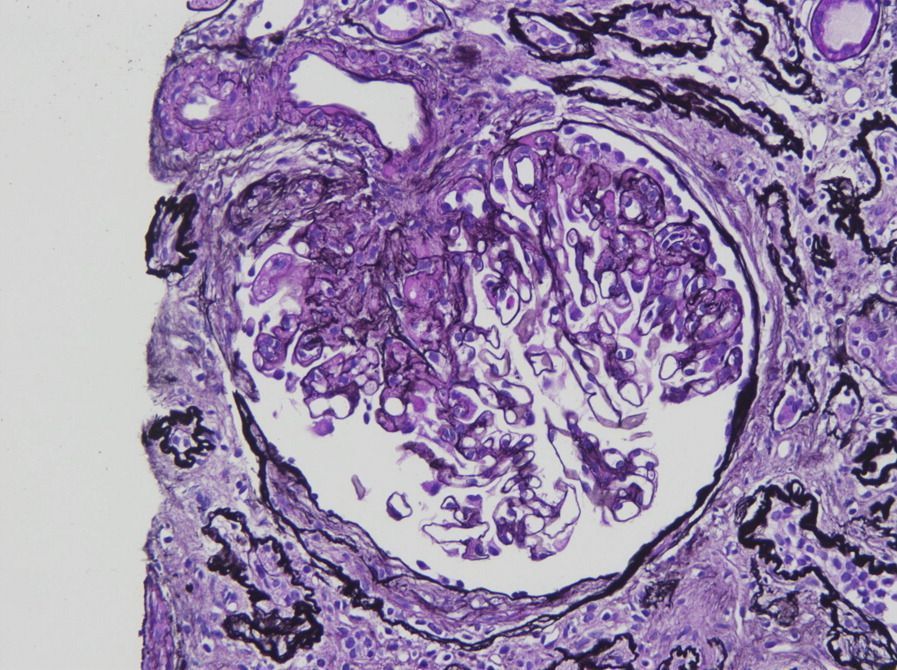

#RenalPath: C1q nephropathy w. segmental sclerosis w. increased mesangial matrix, obliteration of capillary lumens, adhesion to Bowman capsule (right half of tuft) Open left portion of glomerulus shows mild to moderate increase in mesangial cellularity

Hilar variant of focal segmental glomerulosclerosis, with segmental sclerosis at the vascular pole with hyalinosis and adhesion (Jones silver stain)

bit.ly/49P5wQP (FREE)

#FSGS #renalpath